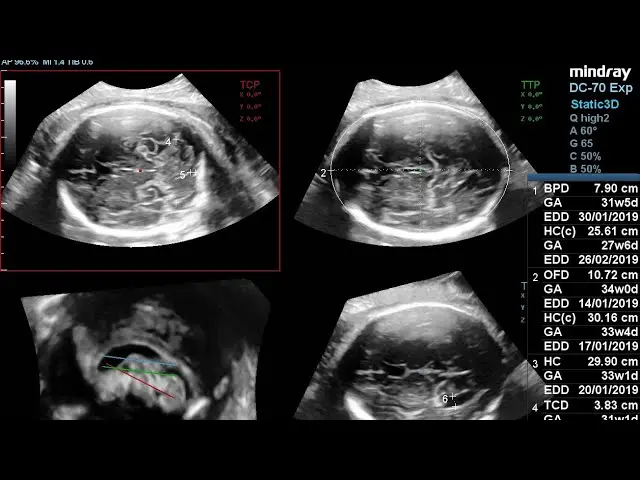

- Modos avanzados de ecografía: Incluye Doppler color y flujo sanguíneo de alta sensibilidad. Elastografía (con variaciones como Natural Touch Elastography) para evaluar la rigidez de tejidos.

- Funciones específicas para Obstetricia/Ginecología: Con herramientas de precisión con adquisición inteligente Smart Planes CNS que permite obtener planos estándar del cerebro fetal y mediciones automáticas confiables. Así como SmartFace, iLive con Hyaline que mejoran el realismo anatómico, permiten rendereado más claro del feto, y mediciones automáticas del feto (BPD, HC, AC, FL).

- Procesamiento rápido de imágenes: Tecnología X‑Engine para acelerar la formación de imágenes y mejorar la precisión, acelera la formación de imágenes, especialmente en modalidades más exigentes como 3D/4D. Reduce latencia / tiempo de procesamiento de imágenes, útil en prácticas de alto volumen.